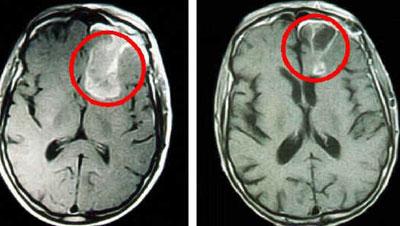

- Раковые образования головного мозга;

За регулирование качества и продолжительности сна отвечает целая система, включающая в себя кору головного мозга, подкорковые, ретикулярные и лимбические его участки. Нарушения в такой системе и вызывают заболевание – гиперсомнию.

От длительного сна страдает сердечнососудистая система, повышается риск получения ишемической болезни сердца. Сбой в режиме сна и активности мозга провоцирует ухудшение памяти, развитие деменции, нарушение мозговой деятельности, появление болезни Альцгеймера.